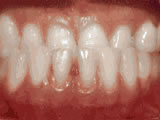

Spacing of teeth

Patient was bothered by the spaces between his teeth. Braces closed the spaces and gave him an ideal bite in 24 months. Special glued-in retainers help keep the spaces closed.